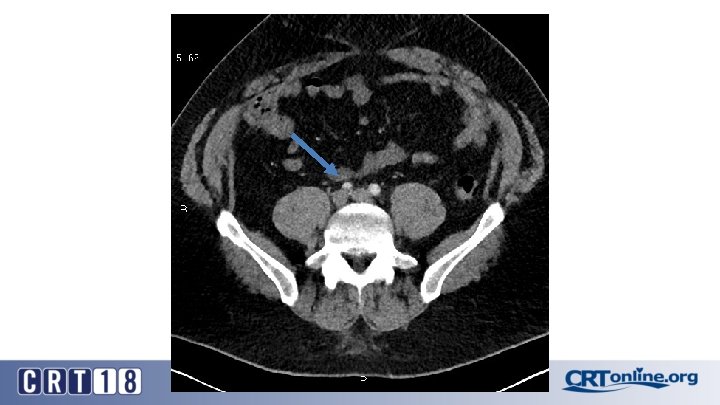

Blue Toe Syndrome

Returns Next day

Failed recanalization: BKA